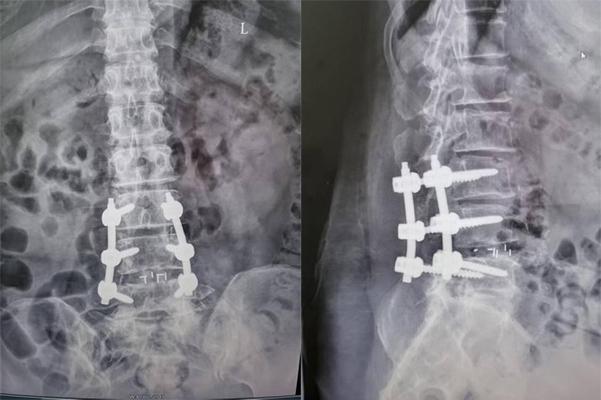

手术在麻醉科团队配合下顺利推进,两位专家精准定位游离椎间盘组织,小心分离粘连部位,完整摘除病变组织,全程120分钟未出现术中并发症,达到预期效果。术后,赵女士在骨科护理团队的专业照护与康复指导下逐步恢复:术后6小时可自主翻身,疼痛明显缓解;术后第2天右下肢肌力恢复至4级+,麻木感减轻;术后1周可在腰围保护下下床活动,踝关节功能基本恢复,行走自如。

出院时,赵女士及家属向医护团队表达谢意。滕宇飞副主任叮嘱,术后3个月内需避免弯腰负重、久坐久站,坚持佩戴腰围并进行腰背肌康复训练,定期复诊以降低复发风险。